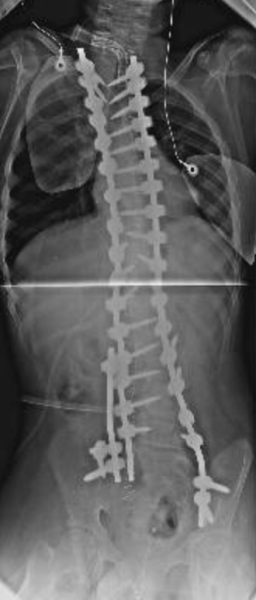

Qui di seguito, un esempio di un paziente affetto da scoliosi severissima, sottoposto a trattamento chirurgico.

Dopo l’intervento:

Schermata 2018-10-07 alle 22.30.15     Schermata 2018-10-07 alle 22.30.39